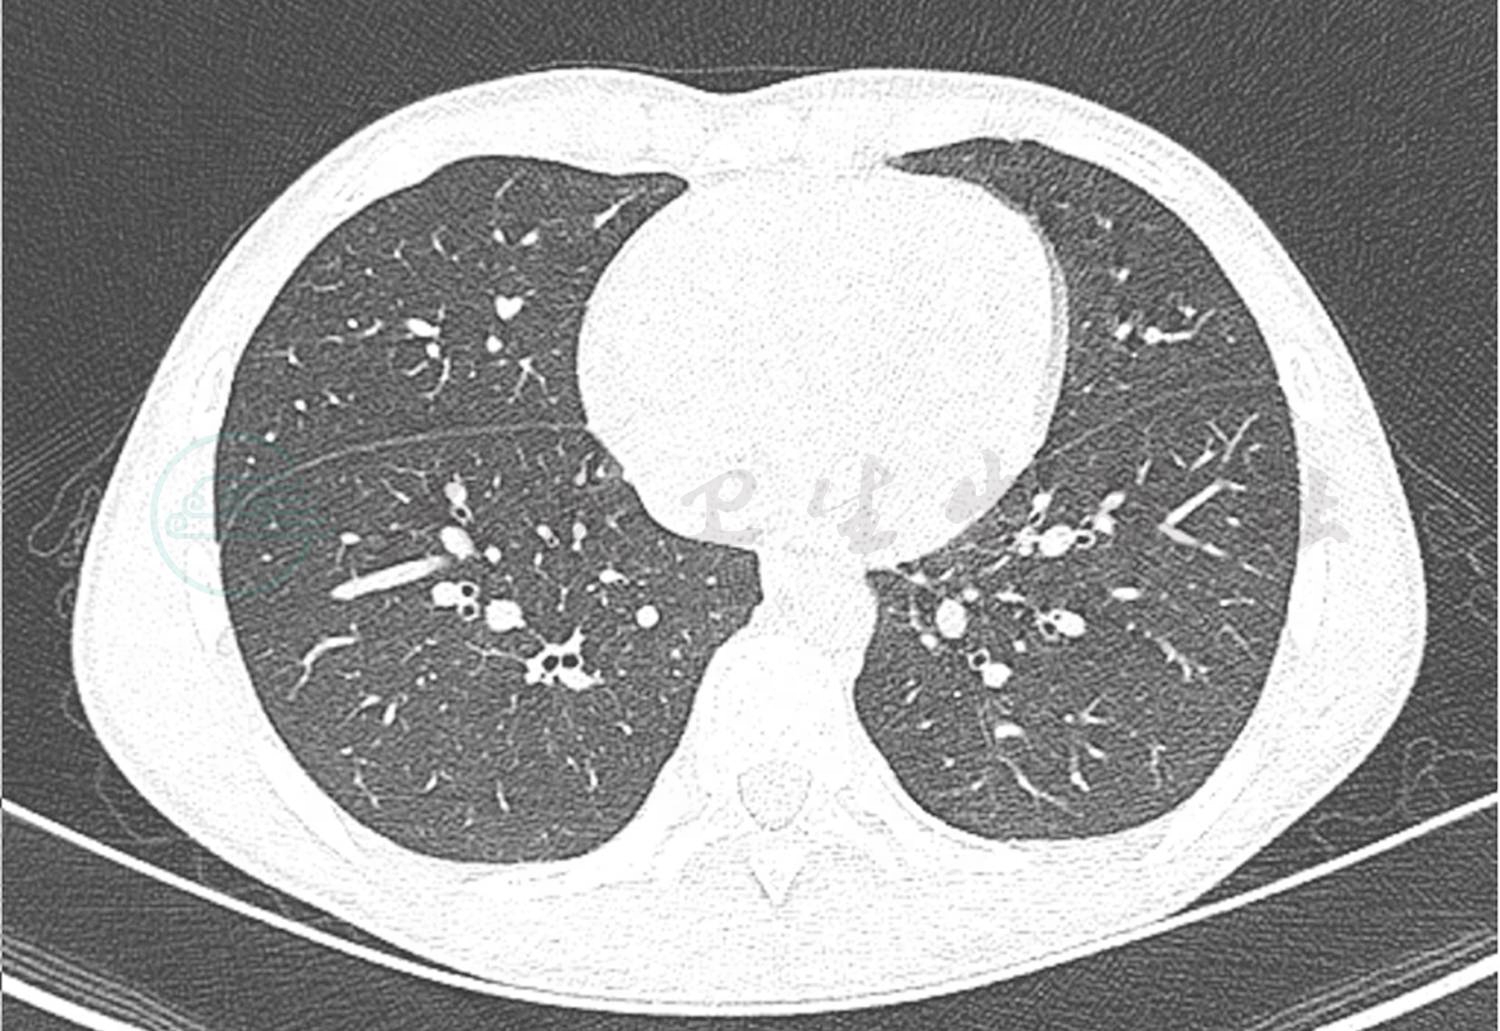

辅助检查:血常规:白细胞计数10.3×109/L,中性粒细胞百分比84.2%,淋巴细胞百分比8.3%,红细胞计数4.36×1012/L,血红蛋白126g/L,血小板 150×1012/L;CRP 87.2mg/L;降钙素原7.22ng/ml;DIC基本正常;肝功能正常;痰培养未见细菌真菌生长;血培养未见细菌生长;6天前肺CT显示双肺多发渗出,以右肺下叶为主伴有实变,双侧胸腔积液(图1);入院前1天肺CT显示双肺下叶实变范围较前增大。双侧胸腔、右侧叶间积液较前减少(图2)。

图2 入院前1天肺CT